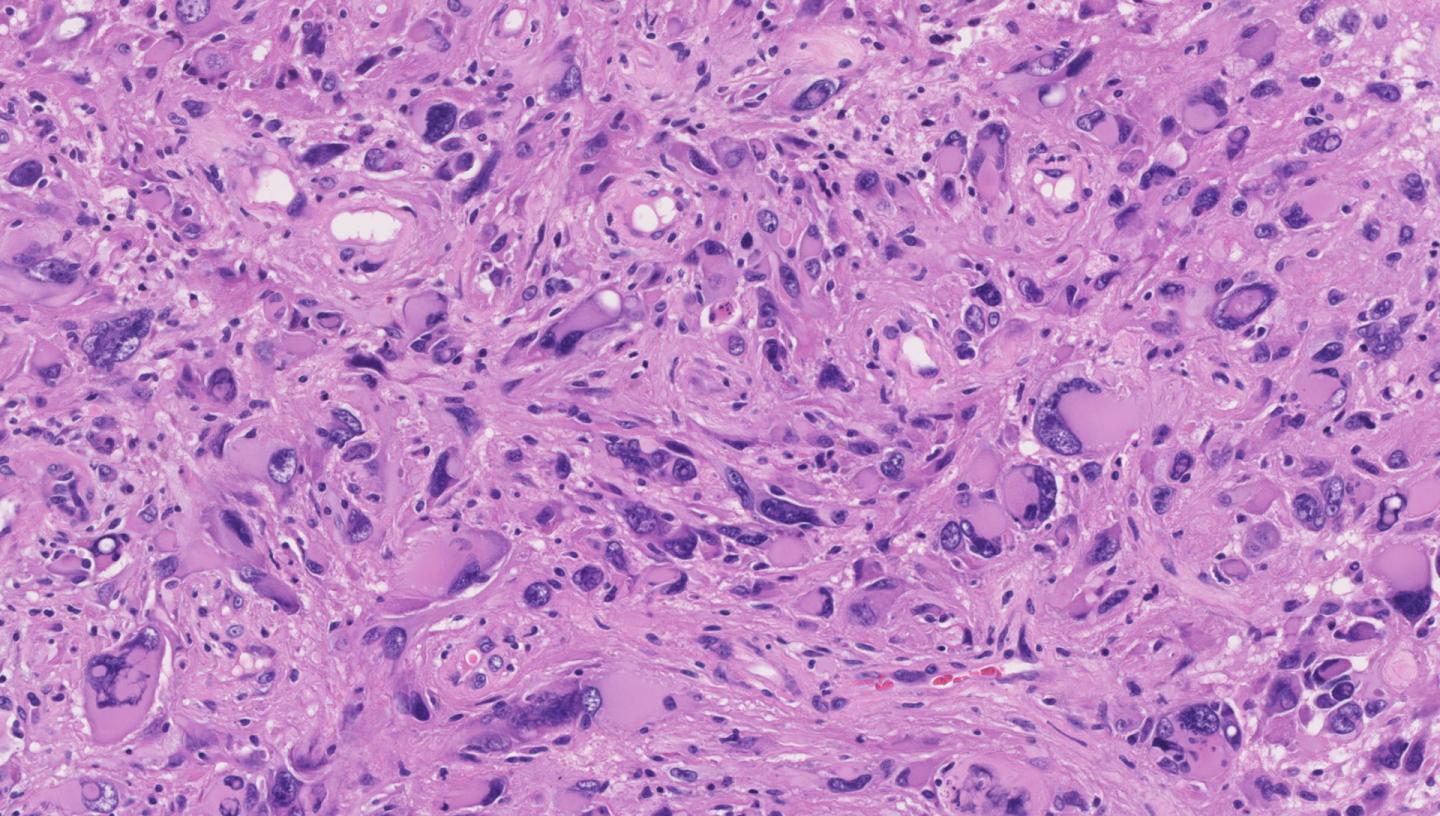

(Vienna, August 27, 2018) Glioblastoma is a highly aggressive brain cancer that predominantly affects people in their 50s, 60s and 70s. Even under the best available care, half of the patients die within one year after diagnosis, and very few live on for more than three years. Many efforts to develop new, targeted treatments have failed over the last decade. The high degree of molecular heterogeneity among the cancer cells results in evolutionary selection for those cells that can withstand drug treatment.

In order to develop better therapies for glioblastoma, detailed knowledge about the molecular heterogeneity of the tumor cells will be crucial, given that this heterogeneity provides the substrate from which drug resistance evolves. Genetic factors such as the amplification of tumor-promoting genes and the deletion of tumor suppressor genes play an important role, but cancer is more than genetics. Recent research suggests a key role of epigenetics, which regulates gene expression and prevents the activation of harmful genes. Whether and how epigenetic regulation changes when a glioblastoma becomes therapy-resistant has been a largely unsolved question.

Combining epigenetic data with brain imaging and digital pathology, the study established important links between glioblastoma at the level of molecules, cells and organs. These associations can be exploited for improving disease classification: "DNA methylation sequencing - as a single test - can be used to predict a wide variety of clinically relevant tumor properties", explains CeMM PhD student Johanna Klughammer who led the data analysis, "providing us with a powerful new approach for characterizing the heterogeneity of brain tumors".